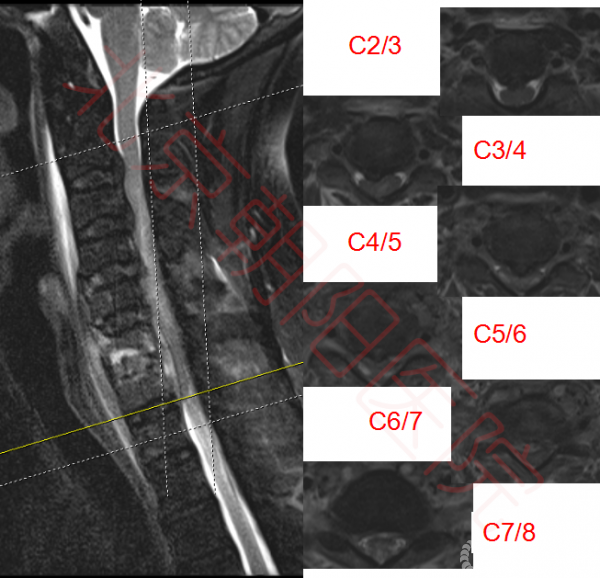

图2:如图可见脊髓多节段受压,C6、C7椎体及椎间盘高信号,C6-C7椎体后方可见高密度影,C5-C8椎体前方高密度影。脊髓内可见高信号区域

图5:C2/3、C3/4压迫仍存在,植骨节段脊髓压迫较术前明显改善